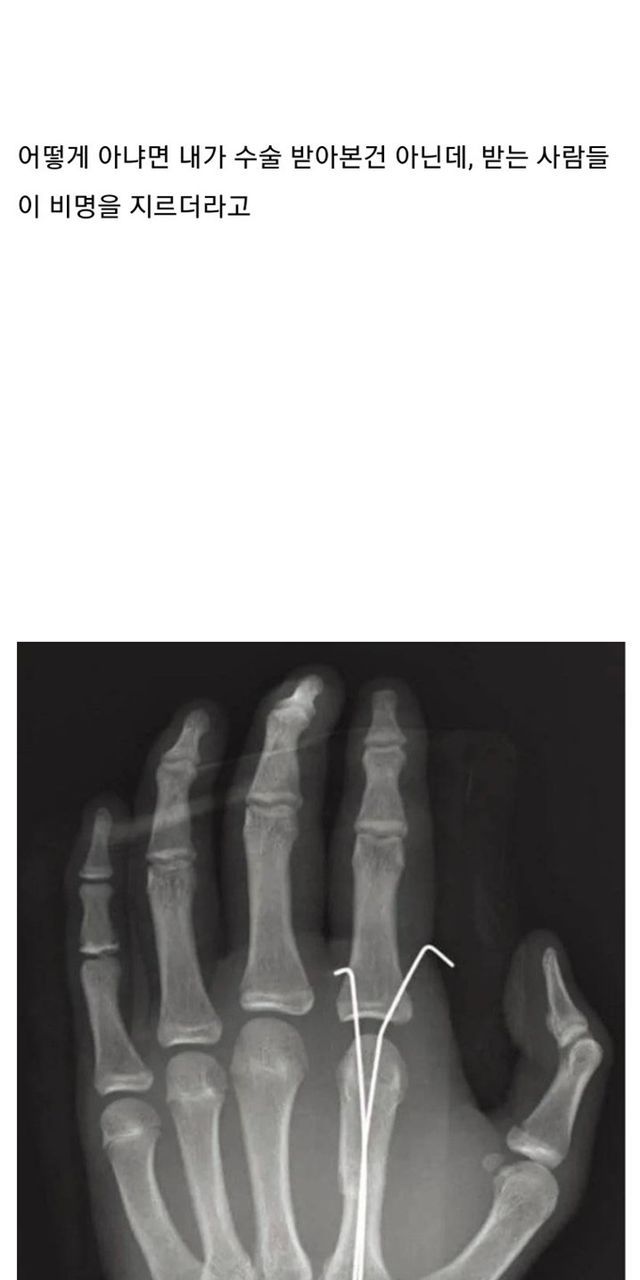

뼈 안부러져본 사람들이 모르는 사실들